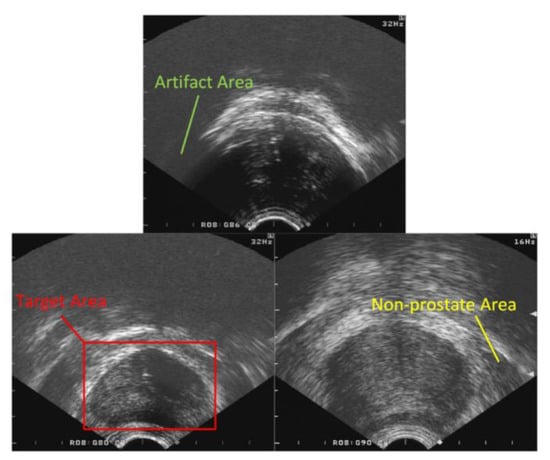

2.2. Target Area Screening Module

2.3. Target Area Screening Module